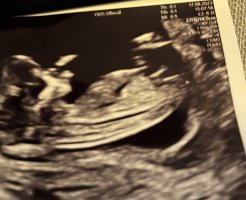

@lyse gul vil du gjette om det er jente eller gutt?Vet ikke om det er mulig å se en nub her?Jordmor ville/kunne vertfall ikke si noe - 14+0

har du flere bilder? synes ikke det er noe tydelig kjønnsorgan på disse.Vet ikke om det er mulig å se en nub her?Jordmor ville/kunne vertfall ikke si noe - 14+0